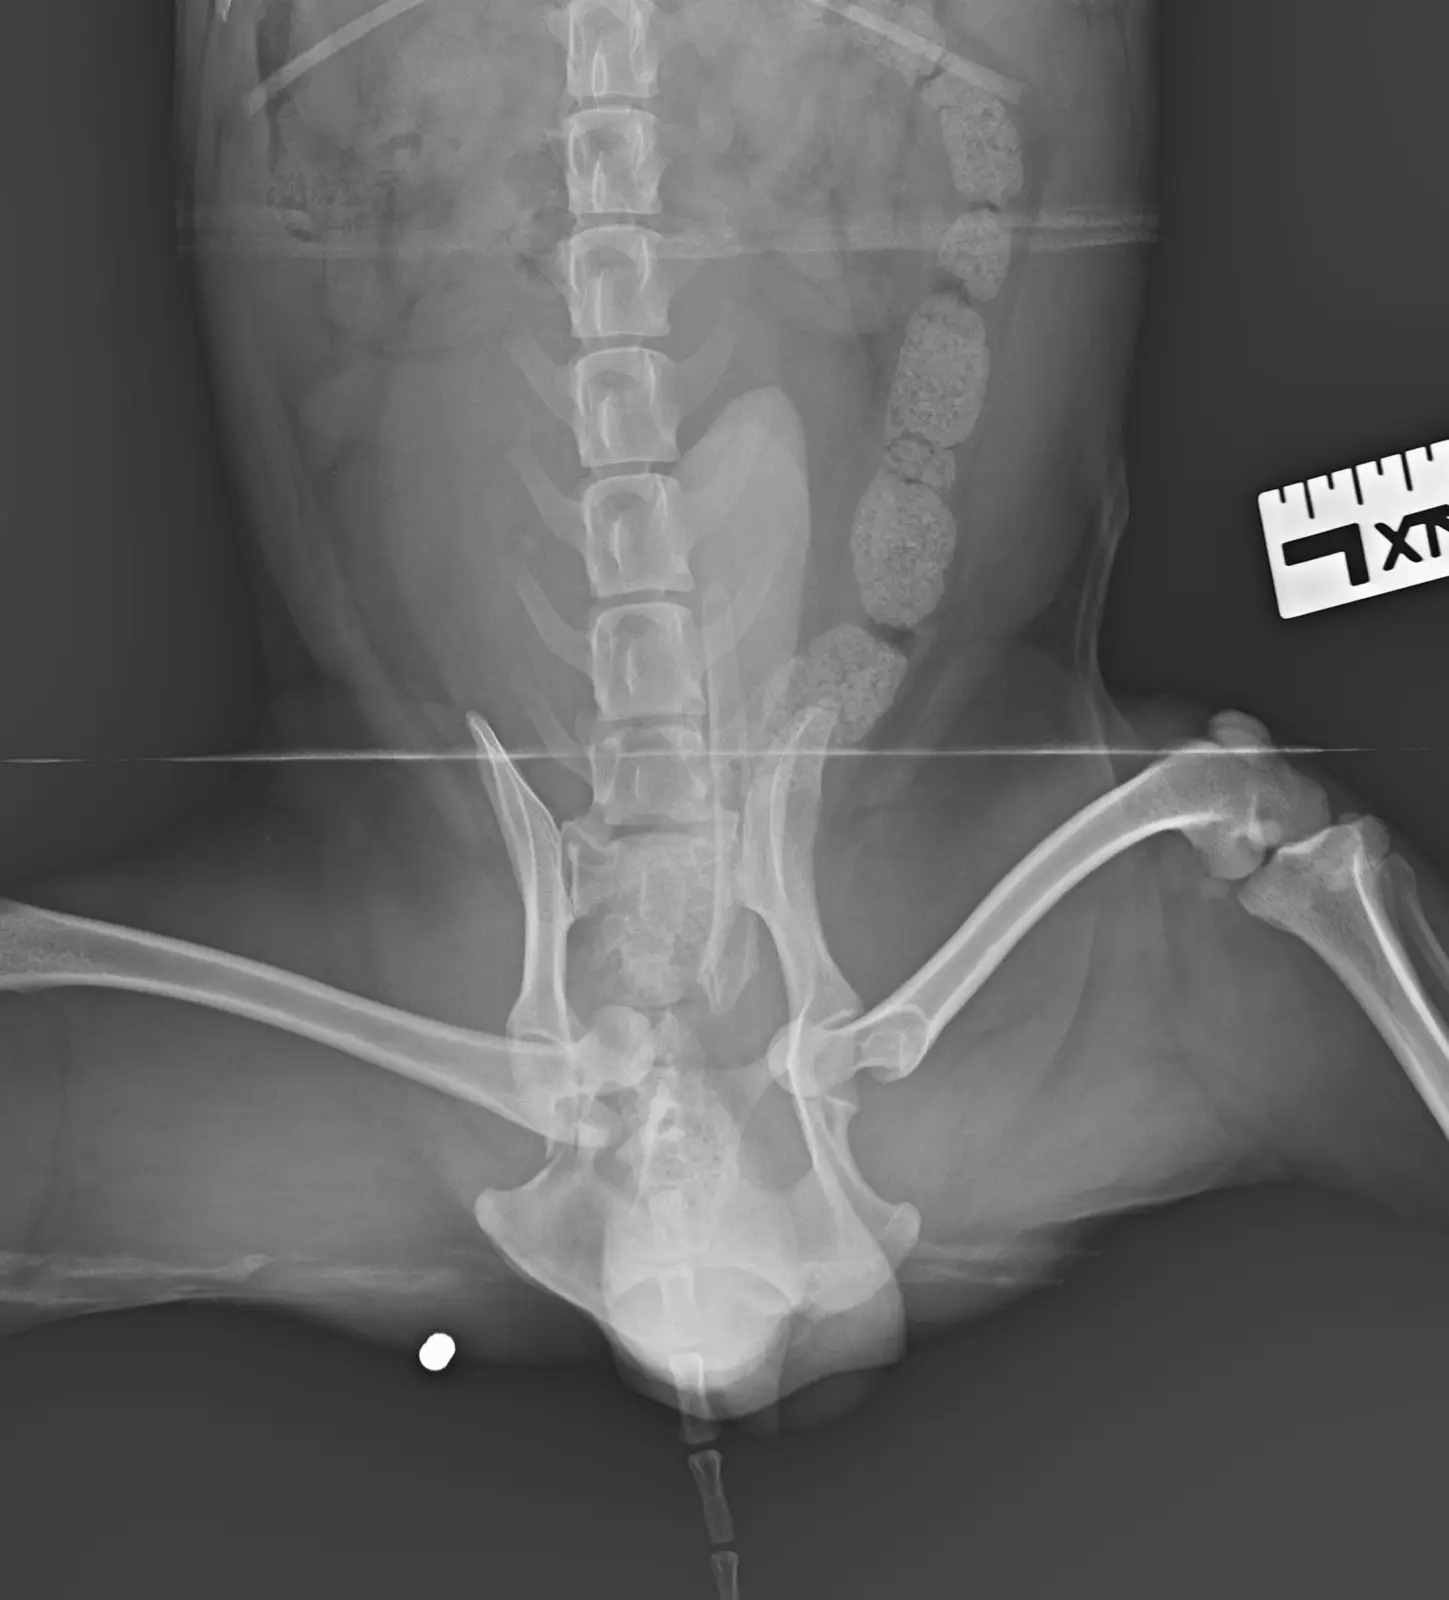

Моля ,който може да помогне !На 29.10 беше първата му операция  за открита фрактура на предна дясна лапа оператор  е  д-р Йордан Стоянов ортопед и на 31.10  беше втората много тежка операция на множество фрактури на таза и за луксациите на двете тазобедрени стави

Please who can help !On 29.10 was his first surgery for open fracture of front right paw operator is Dr. Jordan Stoyanov orthopedist and on 31.10 was the second very severe surgery for multiple fractures of the pelvis and for the luxations of both hip joints